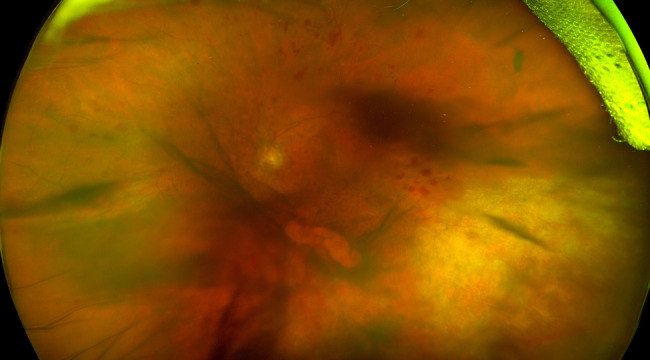

Case presentation: An 80-year-old female presented with one month of blurry vision in the left eye. She was being treated with abatacept, methotrexate, and prednisone for rheumatoid arthritis. Examination revealed anterior chamber and vitreous cell along with peripheral retinal whitening. Fluorescein angiogram showed diffuse retinal non-perfusion. Aqueous fluid PCR testing returned positive for CMV. The retinitis was initially controlled with oral and intravitreal ganciclovir, but then recurred and progressed despite these therapies. Ganciclovir resistance was suspected and the patient was switched to intravitreal foscarnet injections, along with oral letermovir and leflunomide, which lead to resolution of the retinitis. The patient has now continued with letermovir and leflunomide for approximately 2.5 years without reactivation of the retinitis or need for further intravitreal anti-viral injections and with adequate control of her rheumatoid arthritis.

Abstract Image